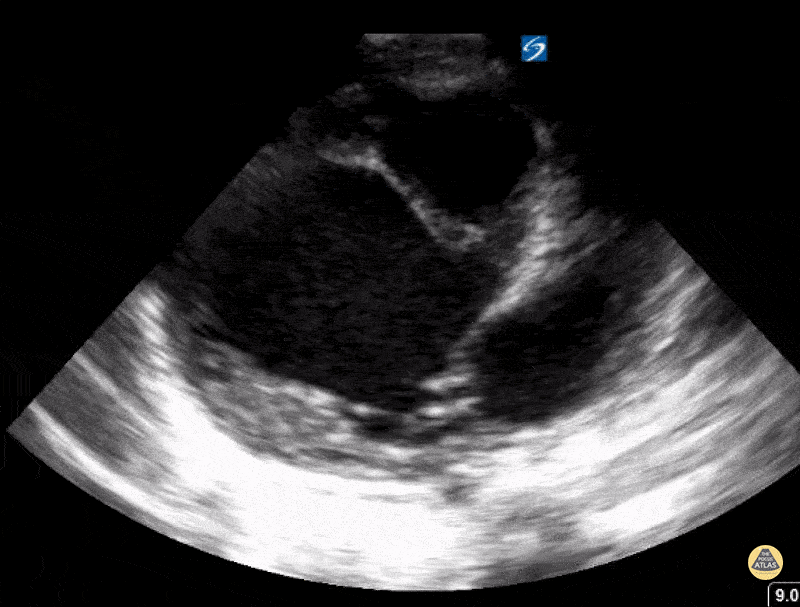

3 month old presenting with respiratory distress. Found to have familial dilated cardiomyopathy. Contributor: Kathryn Pade, MD